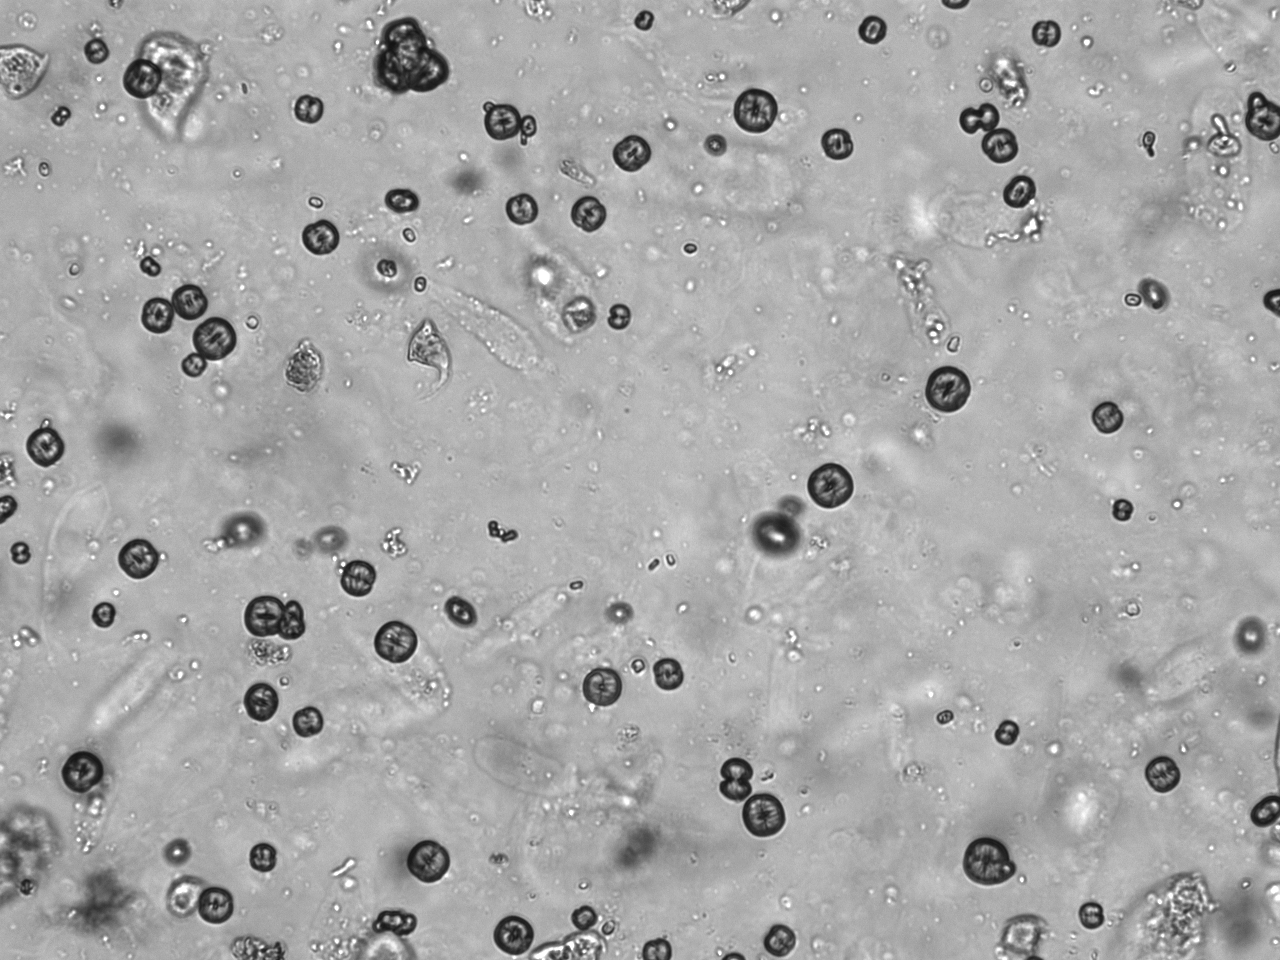

Urin-Feature: Leucinkugeln